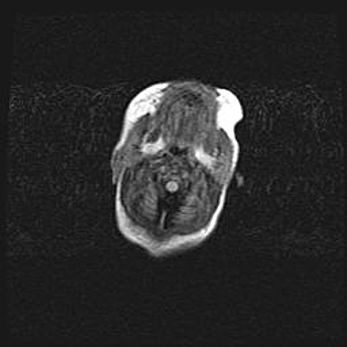

Подострая гематома правой гемисферы мозжечка.

Наружная гидроцефалия.

Возраст: 15 дней

Вес: 3100 г

Пол: женский

Окружность головы: 37 см

Срок гестации: 35-36 недель

При открытой наружной форме гидроцефалии у новорожденных расширяются и переполняются субарахноидные пространства.

Кровоизлияния в мозжечок имеют две клинико-анатомические формы: полушарные гематомы и кровоизлияния в червь.

К появлению этой патологии может привести: повреждения головного мозга, возникающие в результате асфиксии и гипоксии плода при беременности, или травмы во время родов. Редко гематома мозжечка может быть результатом первичной коагулопатии и сосудистой мальформации, диссеминированном внутрисосудистом свертывании, изоиммунной тромбоцитопении.